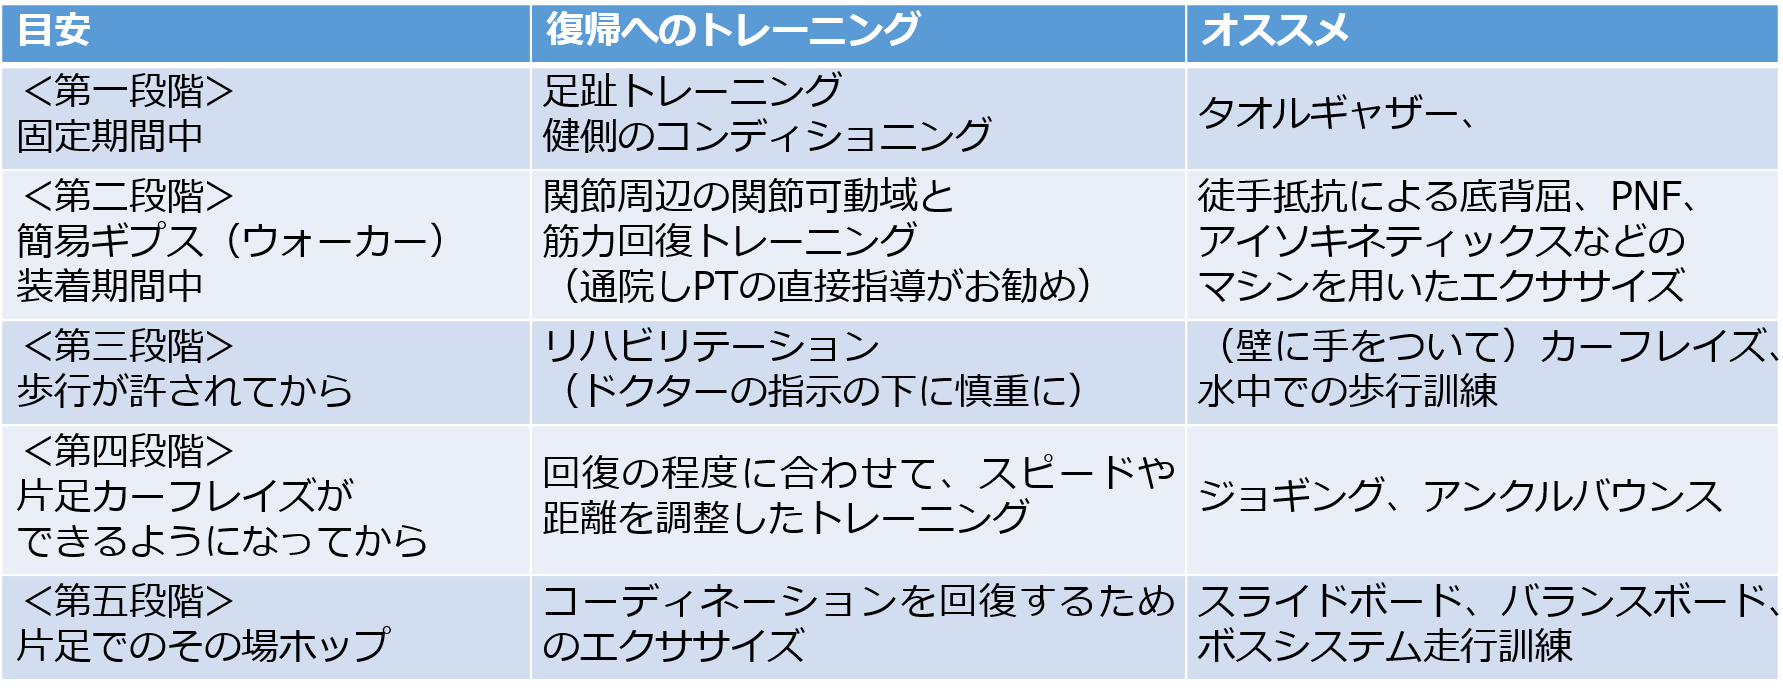

リコンディショニング

受傷直後のリハビリテーションは、保存・手術療法かによって開始時期が異なりますので、ドクターやPTの指示に従ってください。スポーツの現場に出てからも、基本的なメニューは継続しながら、実際の動きに近いトレーニングを処方します。病院では、PNFやアイソキネティックス(等速性運動)などで周囲の筋肉の筋力強化が行われます。

A.固定期間中

アキレス腱断裂の処置は、手術療法にしても保存療法にしてもギプスによる固定期間があります。本来なら、この期間は、病院でPTにリハビリテーションの処方を受ける期間ですが、現場にいる時間もあります。この期間は、患側に関してはギプスをつけたままでのSLRを中心に、健側のコンディショニング(ウェイト・トレーニングや補強運動)を行ってください。ドクターからの処方があれば、この期間中にも、EMSを用いて電気的に筋肉を等尺性収縮させることもできます。また、足指の底背屈もこの期間からスタートして、患部に隣接する筋肉群の活動性を維持します。

B.簡易ギプス(ウォーカー)装着期間中

ギプスが取れてからしばらくの間は、アンクルブレースなどのスポーツ用装具よりも固定力が強く取り外しが可能な、簡易ギプスやウォーカーをつけて日常生活をするようにします。ギプスが取れてからの最初の2~3週間が最も再断裂の危険性が高い期間といわれ、この時期は慎重にリコンディショニングを行う必要があります。基本的には、通院してPTに直接、指導を受けることをお勧めします。内容的には、足関節周辺の関節可動域と筋力を回復するため、徒手抵抗による底背屈やPNF、アイソキネティックスなどのマシンを用いたエクササイズが処方されます。

C.歩行が許されてから

ドクターの指示の下に慎重にリハビリテーションが進められるべきなのですが、机などに手をついてのカーフレイズが可能になると在宅メニューが処方されます。アスリートの場合は、水中での歩行訓練を行います。ゆっくりとした速度での歩行、つま先歩き、踵歩きなどを行います。プールサイドで滑らないよう、要注意です。

壁に手をついてのカーフレイズができるようになったら、陸上での歩行訓練を行います。一般的な歩行に加え、小股のつま先歩き、踵歩きなどを行い、徐々に大またにしていきます。さらに手離しのカーフレイズができるようになったら、シャッキングを行います。シャッキングとは、常にどちらかの足が地面についているようなゆっくりとしたジョギングのことです。

D.片足カーフレイズができるようになってから

床から離れない程度のアンクルバウンスを行います。アンクルバウンスとは、足首を使ってその場ジャンプすることですが、初期の段階では、床から離れない程度でリズムよく行います。慣れてきたら、徐々に高く上がるようにします。

この時期から、積極的にジョギングも行うようにします。腕振りや姿勢などを意識しながら、可能な限り左右のテンポが同じになるようにバランスを大事にしてください。回復の程度に合わせて、スピードや距離を調整するようにしてください。

E.片足でのその場ホップができるようになってから

スライドボード、バランスボード、ボスシステムなど、コーディネーションを回復するためのエクササイズや補強を取り入れます。ジョギングに加えて、サイドステップやスキップ、クロスステップ、バッククロスなどの走行訓練をします。さらに回復が進めば、切り返しや方向転換もメニューに加えますが、最も危険なのはバック走から急激な方向転換をしてダッシュすることです。注意してください。チャイナステップなどもこの時期に行うとよいでしょう。